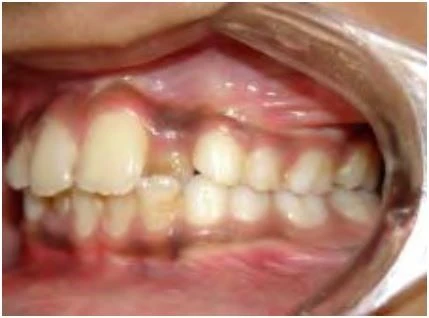

Khớp cắn nằm về phía trước so với bình thường

Với loại này, khi các răng gặp nhau tại khớp cắn trung tâm thì cung răng hàm dưới nằm về phía trước hơn.

Khớp cắn nằm về phía sau so với bình thường

Ở đây, khi các răng gặp nhau tại khớp cắn trung tâm thì cung răng hàm dưới nằm về phía sau hơn.